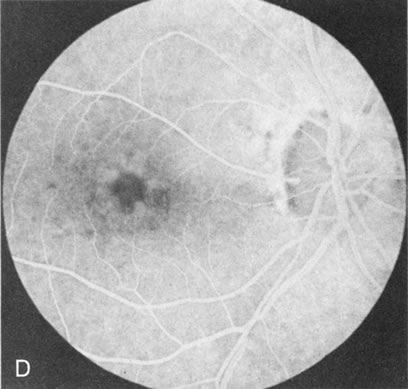

Fig. 1. Retinitis pigmentosa. A. A typical area of bone spicule pigmentation. B. Diffuse dye leakage is apparent throughout the posterior pole. C. The early angiogram shows dilated and irregular retinal radial peripapillary capillaries and perifoveal retinal capillaries. D. Leakage from these vessels are evident in the late angiogram.

Dye leakage in RP may occur from the retinal vessels or at the level of the retinal pigment epithelium (Fig. 1B).2–4 The leakage may be seen in the macula and posterior pole, along the vascular arcades in the distribution of the radial peripapillary capillaries, and in the periphery (where an exudative vasculopathy resembling Coats' disease is suggested).

Of more clinical importance is the role of FA in the diagnosis and treatment of cystoid macular edema (CME) (Fig. 1C and D). Stereoscopic FA indicates that the leakage, which may be diffuse or have the typical petaloid stellate appearance of CME, can come from the perifoveal retinal capillaries, from the choroid through the RPE, or from a combination of both sources.4 With the recent suggestion that CME in RP may be successfully treated with acetazolamide,5, 6 FA is thus important to document the diagnosis of CME, establish the origin(s) of leakage, and follow patients during and after therapy.